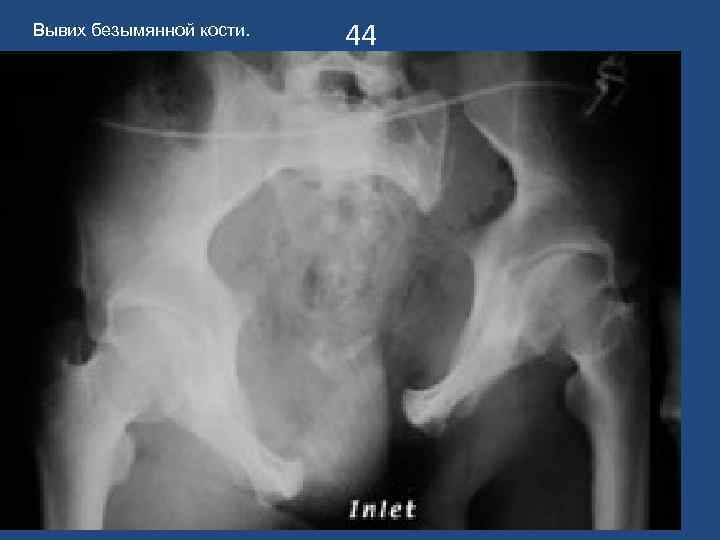

Вывих безымянной кости. 44